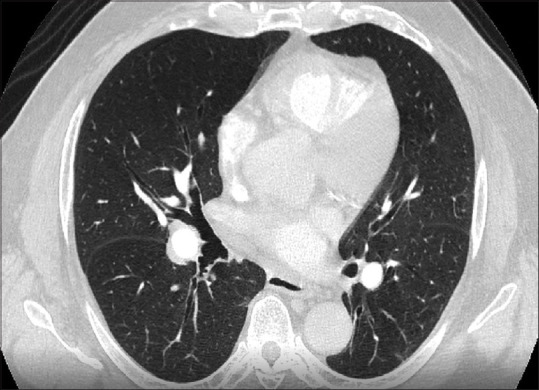

Abstract: This study describes the perioperative management of a 68-year-old Jehovah's Witness patient with chronic pulmonary thromboembolism, multiple comorbidities, and undergoing pulmonary thromboendarterectomy. The patient had a satisfactory perioperative evolution, demonstrating the feasibility of this complex procedure in this population with a comprehensive and timely approach, complemented by an evaluation from a multidisciplinary team.

Abstract Image